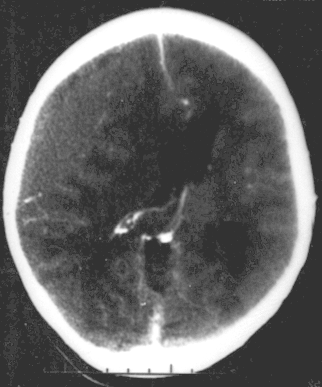

Es un sangrado entre la parte interior del cráneo y la cubierta externa del cerebro (denominada "duramadre").

Un HE también se puede presentar cuando hay ruptura de un vaso sanguíneo, generalmente una arteria. El vaso sanguíneo sangra en el espacio que queda entre la duramadre y el cráneo.

Un sangrado rápido causa una acumulación de sangre (hematoma) que presiona el cerebro. La presión dentro de la cabeza (presión intracraneal, PI) aumenta rápidamente. Esta presión puede ocasionar una lesión cerebral adicional.